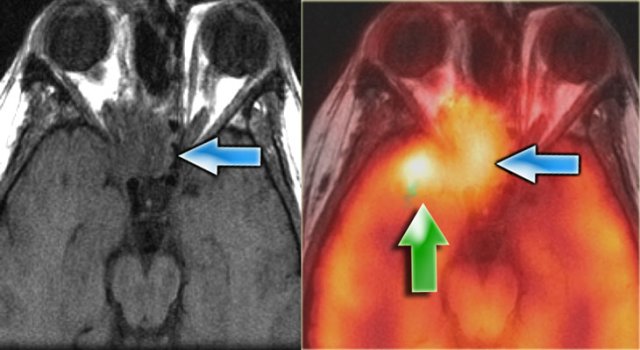

Lymphoma pretreatment Lymphoma pretreatment

Imaging can also be used to monitor treatment response.

This patient had a skull-base B-cell lymphoma.

Pre-treatment we see the extent of the lesion, which is FDG-avid.

Lymphoma 3 months post-chemoXRT Lymphoma 3 months post-chemoXRT

Three months into therapy the skull-base mass has resolved.

There is no more pathological FDG uptake, and there is remineralisation of the bone.

Recurrent sinus carcinoma Recurrent sinus carcinoma

The patient on the left had a resection of a carcinoma.

Now there is a recurrence (blue arrow on MR and fusion image).

The green arrow, however points to post-radiation tissue changes.